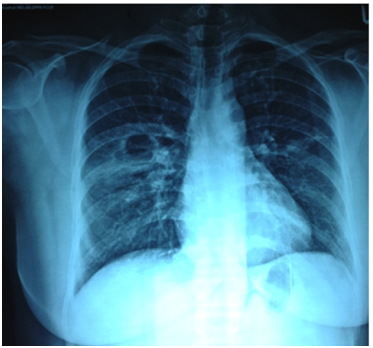

With the use of RC Cornet (Figure 1) along with conventional chest physiotherapy the patient improved better when compared to the day of admission and it was evident subjectively. The quantity of the sputum was reduced since the weight of the sputum mug was 0.5 g and her respiratory rate was 16 breaths per minute post treatment. The perception of dyspnea was reduced due to improvement in gaseous exchange since the secretions block the air passages. After the treatment, the rate of perceived exertion according to Borg scale was 9. On auscultation there were no crepitations and air entry was equal. The percentage of saturation of oxygen was 100% room air. There was also good improvement in radiological findings before and after the treatment and it was shown in (Figures 2 & 3) respectively. When we compared the X-ray findings during the time of admission and 10 days after the treatment, consolidation was markedly reduced and the patient responded well for the treatment.

Figure 2 Chest X-Ray at the time of admission.